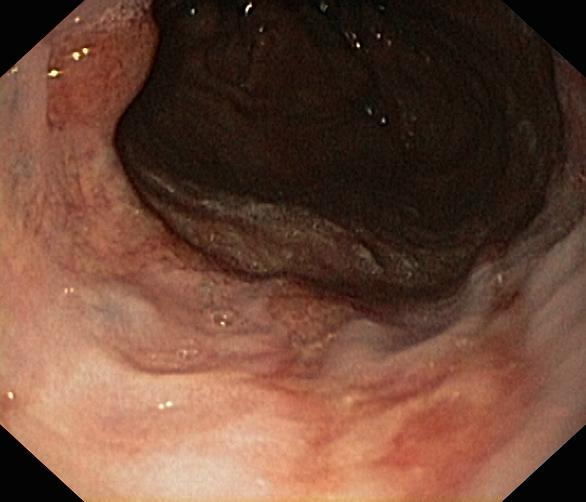

Choroba refluksowa